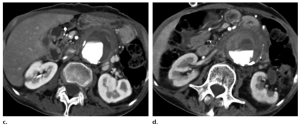

Hình 10. Loét mảng xơ vữa xuyên thành (PAU) tiến triển thành phình động mạch dạng túi (saccular aneurysm) trong hơn 2 năm ở bệnh nhân nữ 61 tuổi. Hình ảnh CT với MPR mặt phẳng axial (a) và coronal (b) ban đầu, hình ảnh theo dõi sau 1 năm trên mặt phẳng axial (c) và coronal (d) và hình ảnh theo dõi sau 2 năm trên mặt phẳng axial (e) và coronal (f) cho thấy sự lan rộng ra dần dần của vết loét xuyên thành ở phía trên (mũi tên) ở động mạch chủ ngực xuống.